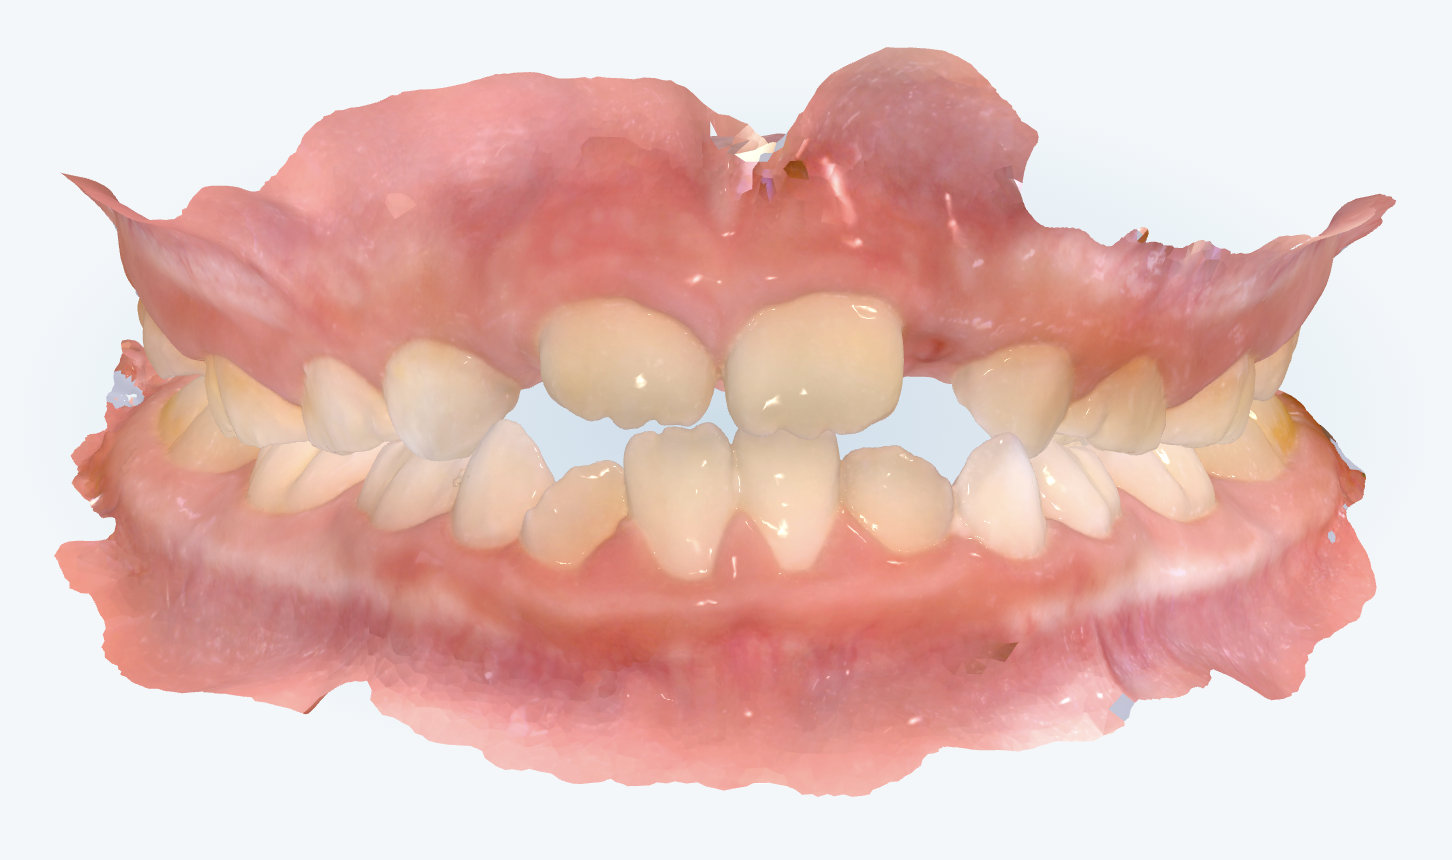

初診時の画像診断

上下の歯並びにガタガタが見られました。特に上の歯並びの前から2番目の歯は生えるスペースが足りないです。

左上の前から3番目の乳歯の上下の噛み合わせが上下反対でした。